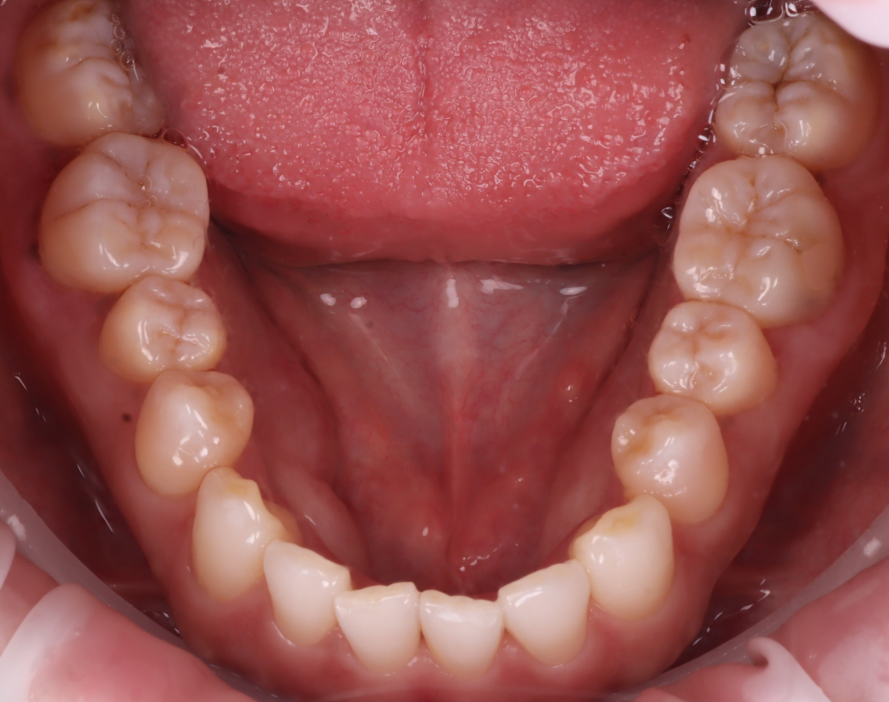

또, 윗니와 아랫니가 워낙 깊게 물리고 있었습니다.

그래서 치아를 좌, 우로 움직일 때 아랫니와의 간섭이 많이 되어 아래 앞니를 조금 다듬어야 할 수도 있음을 설명드렸습니다.

아래 앞니가 고르지 않고, 조금씩 틀어진 부분이 있어 그 부분이 걸릴 수 있겠더라고요.

그래서 이 부분은 레진이 완료된 후 확인해 보기로 했습니다.

촬영일 : 251203